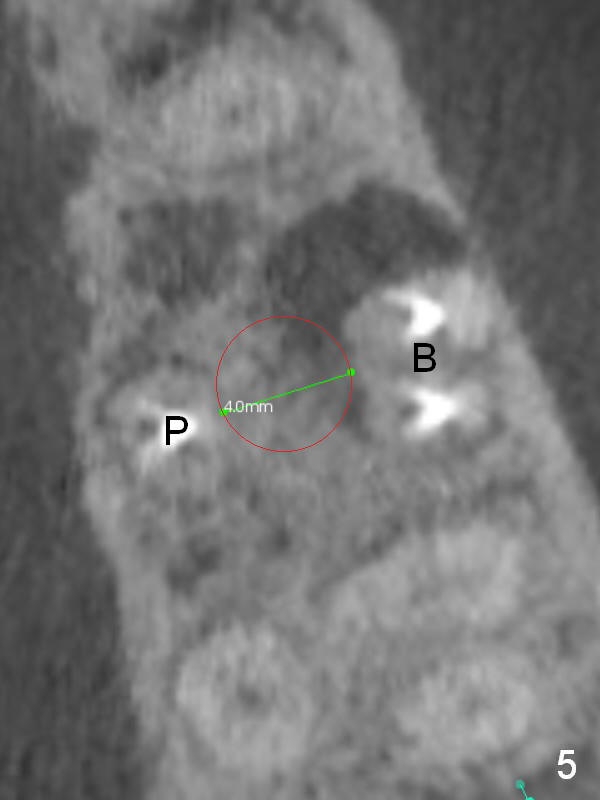

A 34-year-old man has persistent large periradicular radiolucency (Fig.1) after root canal therapy with a fistula (Fig.2). It appears that immediately after extraction (no Antibiotic) a long implant (15 or 16 mm, green outline) should be placed to bypass the bony defect with 2-point fixation (septum and sinus floor; Fig.3 (CBCT sagittal section), 4 (coronal section) red line). A shorter implant, which is placed at the septum (4-5 mm tall), is not expected to be stable. The diameter of the implant is to be determined after sequential osteotomy. The minimal will be 4 mm (Fig.5 axial section) as long as the implant or osteotomy does not perforate the palatal (P) or buccal (B) socket substantially. The bone density at the septum and the sinus floor is 1100 and 200-400 units, respectively. Drills and osteotomes (Tatum or Magic Expanders) will be used for osteotomy in these 2 segments, respectively.